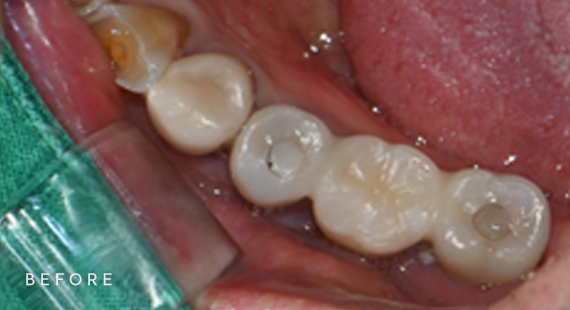

충치치료